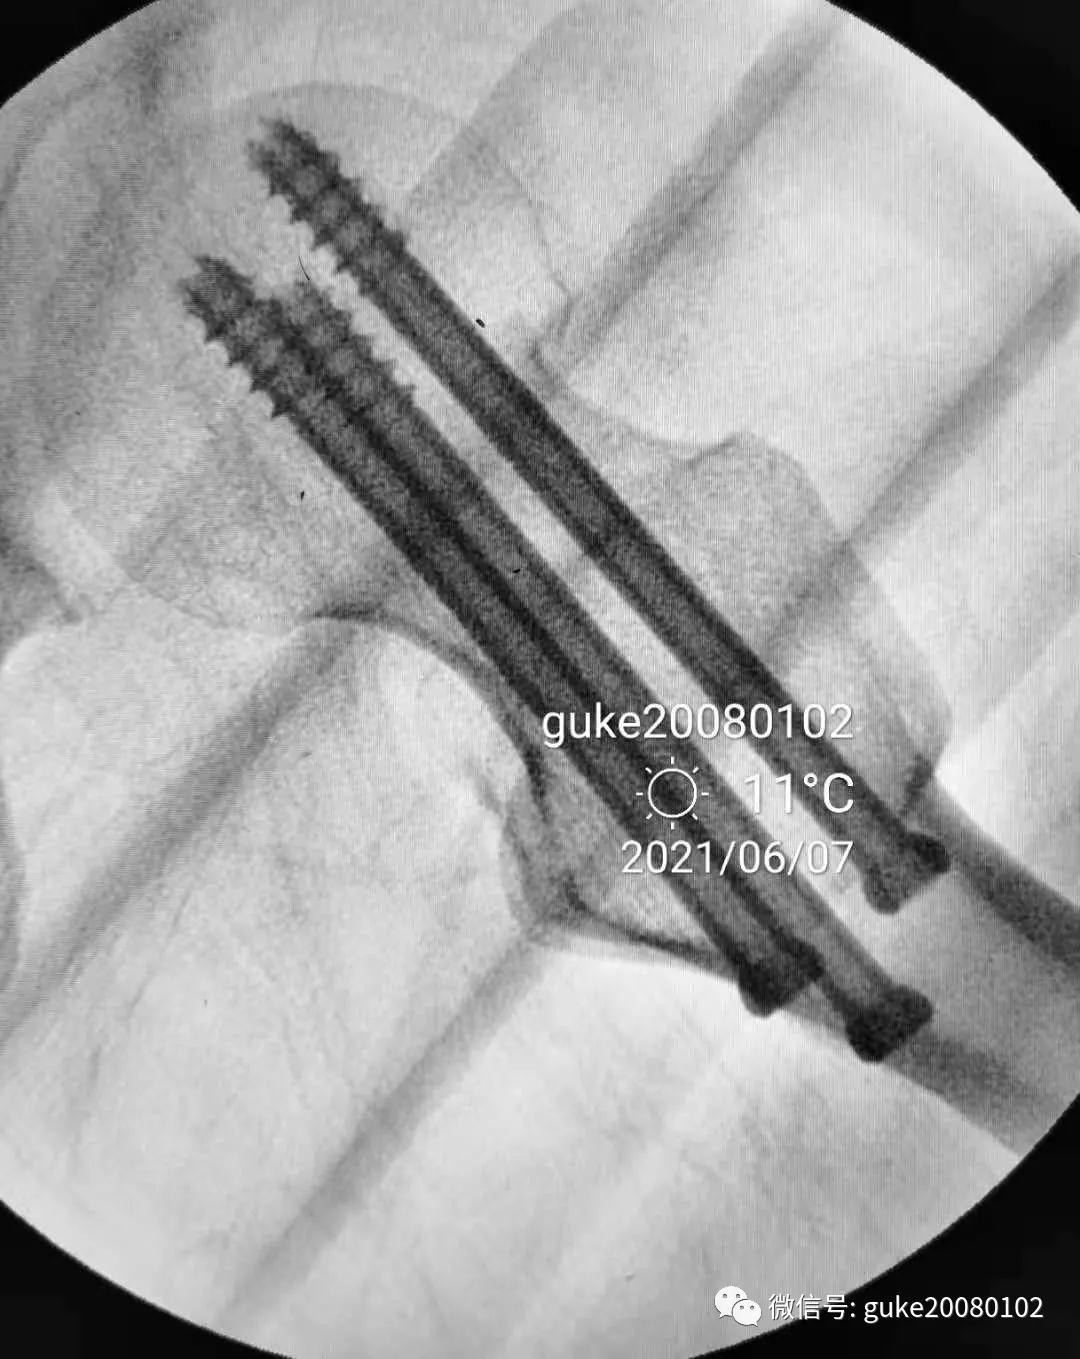

1、植入的第一枚克氏针,前倾和颈干角均满意。将其作为标志针。

2、植入第二枚导针,调整前倾和颈干角。

3、数次调整三枚导针到最合适的位置。